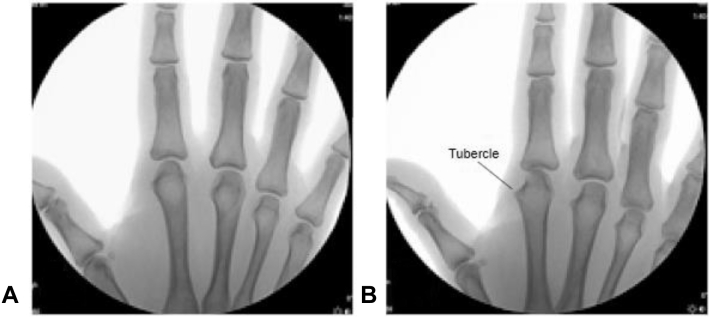

We found that the patients demonstrated a prominent-appearing dorsoradial index finger metacarpal tubercle on fluoroscopic or plain film imaging (Fig. 2), which was best visualized using a 45° to 60° pronated oblique view. We believe that this tubercle may be more prominent or enlarged in patients presenting with focal pain at this site, and that an increase in size may also correlate with patients’ age. However, we have no objective measurements for comparison. These suspicions are based on subjective clinical experience within this small patient population. Future studies could investigate a correlation between tubercle size in symptomatic individuals (afflicted hand vs contralateral hand) as well as age-matched controls.

Figure 2.

Fluoroscopy visualizing a prominent bony tubercle on the tubercle on the right index finger metacarpal. A Posteroanterior view. B Tubercle is best visualized using a 45° to 60° pronated oblique view.